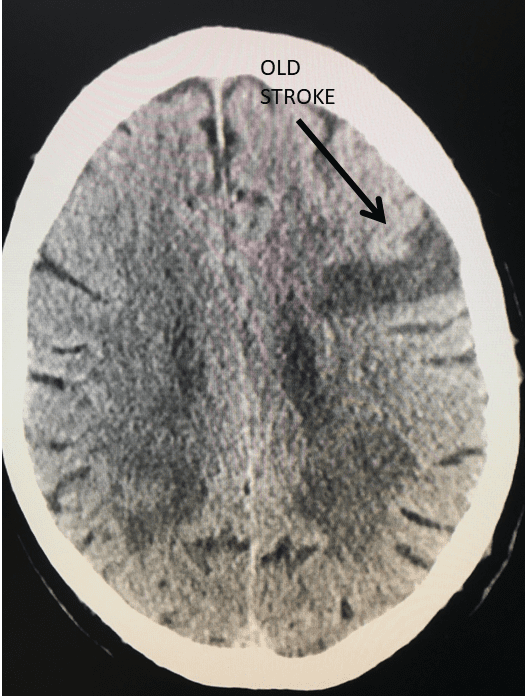

Figure 3.

Catheter angiography prior to angioplasty revealed critical stenosis (Figure 2). Angioplasty was therefore performed under local anesthesia with an embolic protection device deployed to catch any dislodged debris (Figure 3). After angioplasty, a stent was opened across the lesion to maintain long-term patency (Figure 4). Post-stent angiography showed smooth dilatation of the lesion. The patient’s aphasia continued to improve at his 6-week follow-up visit and duplex revealed no significant stenosis through the stent.